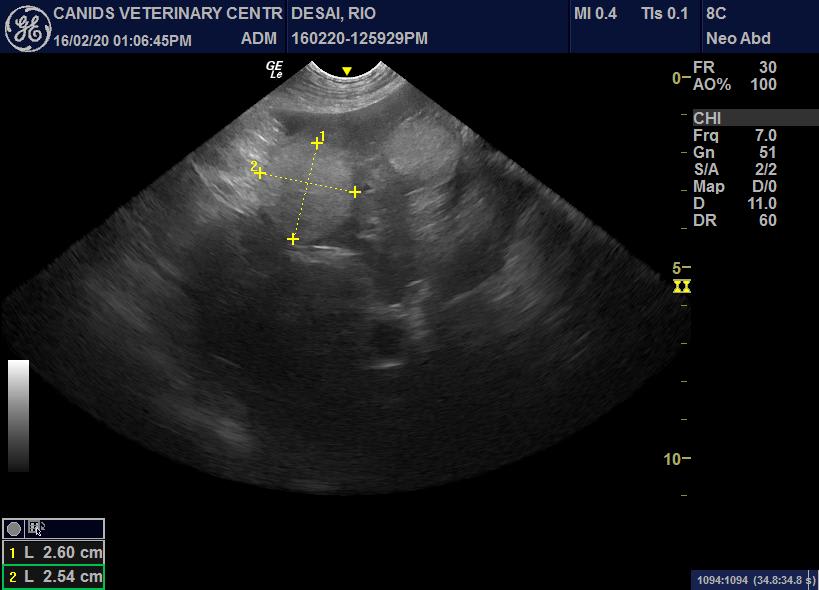

Hello , my dog rio hadn’t been eating anything at all for 7 days now , prior to that he used to eat something here and there , we’ve been to our vet, here are his reports and as for him not eating we’ve kept him on saline and vitamin injections for 15 days now . Firstly they diagnosed with jaundice and now they’ve seen patches in the liver . PS : they’re suggesting to have a biopsy done , but we’re too scared for him because we’ve not had a firm answer from any of these doctors .

Thanks for using Petco Pet Education Center, formerly Petcoach! I’m sorry to hear Rio isn’t feeling well. I would recommend having the biopsy to find the reason for the elevated liver enzymes. They can’t give you an answer because they don’t have enough information. Elevated liver values isn’t enough to say why. They biopsy should give more information. I would also recommend having them test for leptospirosis. They can also test bile acids for liver function. I hope this helps and you find an answer. Good luck and kisses to Rio!